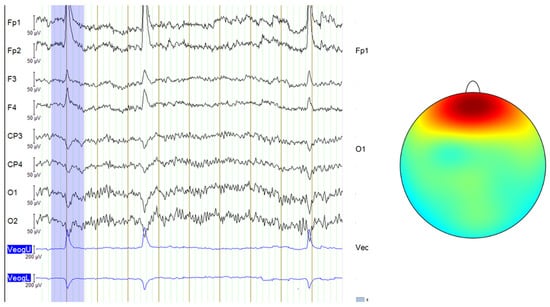

In this study, even though the acquisition protocol for all databases used required subjects to keep their eyes closed, some signals from the DR database still exhibited micro-blink artifacts or other eye movements similar to blinking, likely caused by muscle contractions. These artifacts are visible on the EEG recording and are characterized by very large amplitude spikes, as seen in Figure 3. The signals from the MDD database and the self-collected data followed a consistent eyes-closed acquisition protocol, leading to cleaner signals without such noise. Therefore, only some signals from the DR database required filtering using ICA to remove these micro-blink artifacts or muscle-induced eye movements.

In contrast, although the DR database was collected under a closed-eye protocol, some signals still contain blinking artifacts, as illustrated in Figure 5.

To eliminate this noise, independent component analysis (ICA) was employed.

An eight-component representation was chosen, from which the component labeled “ICA000” was identified as corresponding to the blinking artifacts. This component was removed, and the signal was then reconstructed.

Figure 3. Blink artifacts in EEG data, with the last two channels representing an EOG signal that records eye movements (left) and the topographic map showing the typical scalp distribution of blinks (right—color gradients represent electrical activity across the scalp and red indicates high positive voltage, concentrated around the frontal electrodes) [10].